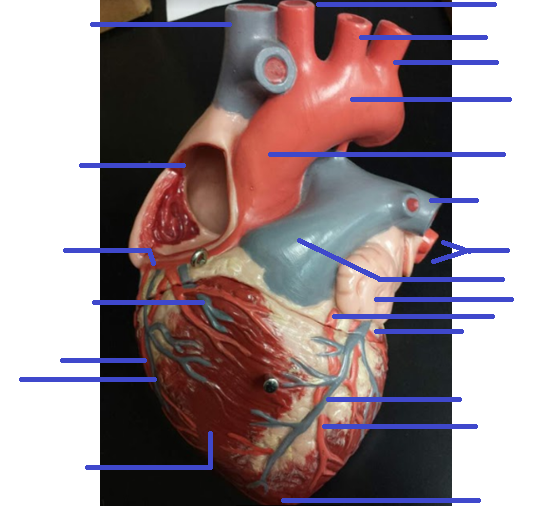

Name the missing parts.

External posterior view

Name the missing parts.

External posterior view

Name the missing parts.

External posterior view

Name the missing parts.

External anterior view

Name the missing parts.

Frontal section